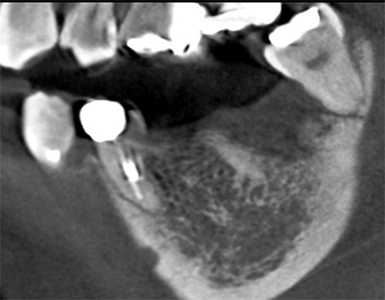

CASE2

抜歯窩保存術 インプラント埋入術

初診時

左下7抜歯時

骨造成4か月後

インプラント手術後

年齢・性別 55歳・女性

主訴 左下の奥歯より嫌な匂いがする

診断名 左下第二大臼歯 歯根破折、慢性根尖性歯周炎

治療内容 左下7の歯根破折に起因する慢性根尖性歯周炎により抜歯が必要となった。患者様は機能性と審美性の回復を強く希望したため、抜歯後骨造成を行いインプラント治療を行った。

(GBR:歯根破折の炎症により、抜歯窩周囲の骨吸収が進んでおりこの状態ではインプラントを安定して埋入するだけの十分な骨量がないと判断し、GBR(骨造成)を行った。)

インプラント体と骨が強固に結合するまで通常3~6か月の治癒期間を設るため、インプラント体を埋入し、3か月経過後骨との結合を確認した後、型取りを行い仮歯で問題ないことを確認し、セラミックの人工歯(上部構造)を装着して治療完了した。

治療期間 インプラント埋入前に中断があったため1年7か月→初診からインプラント治療完了まで

費用 骨造成:110,000円

インプラント2本:902,000円(1本の場合は544,500円)

リスク・副作用 術後の痛み、腫れ、出血が出ることがある

感染の可能性、腫れや再生不良が起こることがある

喫煙や清掃不良、炎症が重度の場合は組織再生の効果が十分得られないことがある